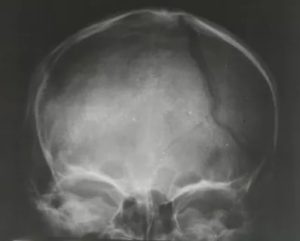

Далее доктор направляет больного на процедуру рентгенографии, которая выполняется в двух проекциях. Если травма является серьезной, то при диагностике тело не меняет своего положения, а передвигается только трубка рентгеновского аппарата.

Для постановки точного диагноза и составления прогноза выздоровления ребенку проводят рентгенологическое исследование. Краниография позволяет получить четкое изображение, но качественно расшифровать его сможет только опытный врач.

Важно не спутать трещины с сосудистой сеткой и черепными швами. Особенно тяжело отличить трещины, когда они переходят с теменной кости на лобную или затылочную области. Линия разлома имеет черный цвет. Она прямая и узкая без каких либо разветвлений.

При этом сосуды и швы имеют более светлый цвет.

Диагностика перелома теменного сегмента осуществляется с помощью рентгенографического аппарата. Снимок делается в двух проекциях: прямой и боковой.